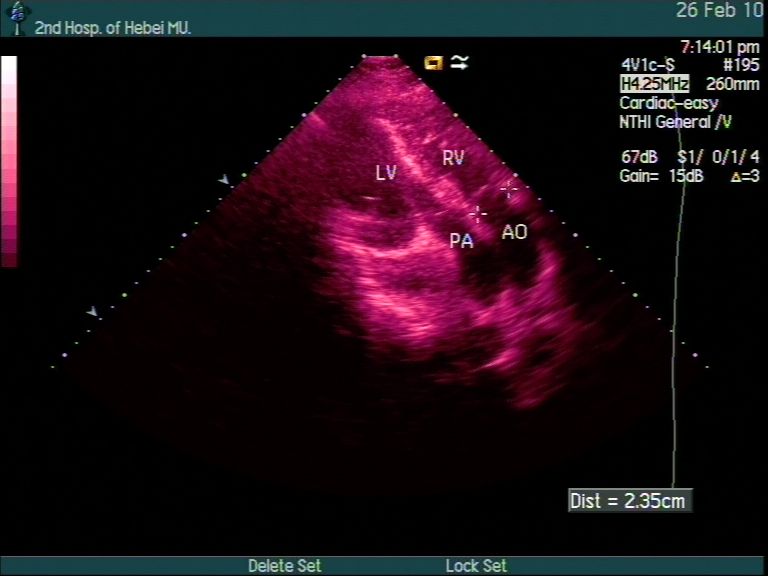

疑似主动脉瓣脱垂的主动脉夹层超声心动图诊断分析